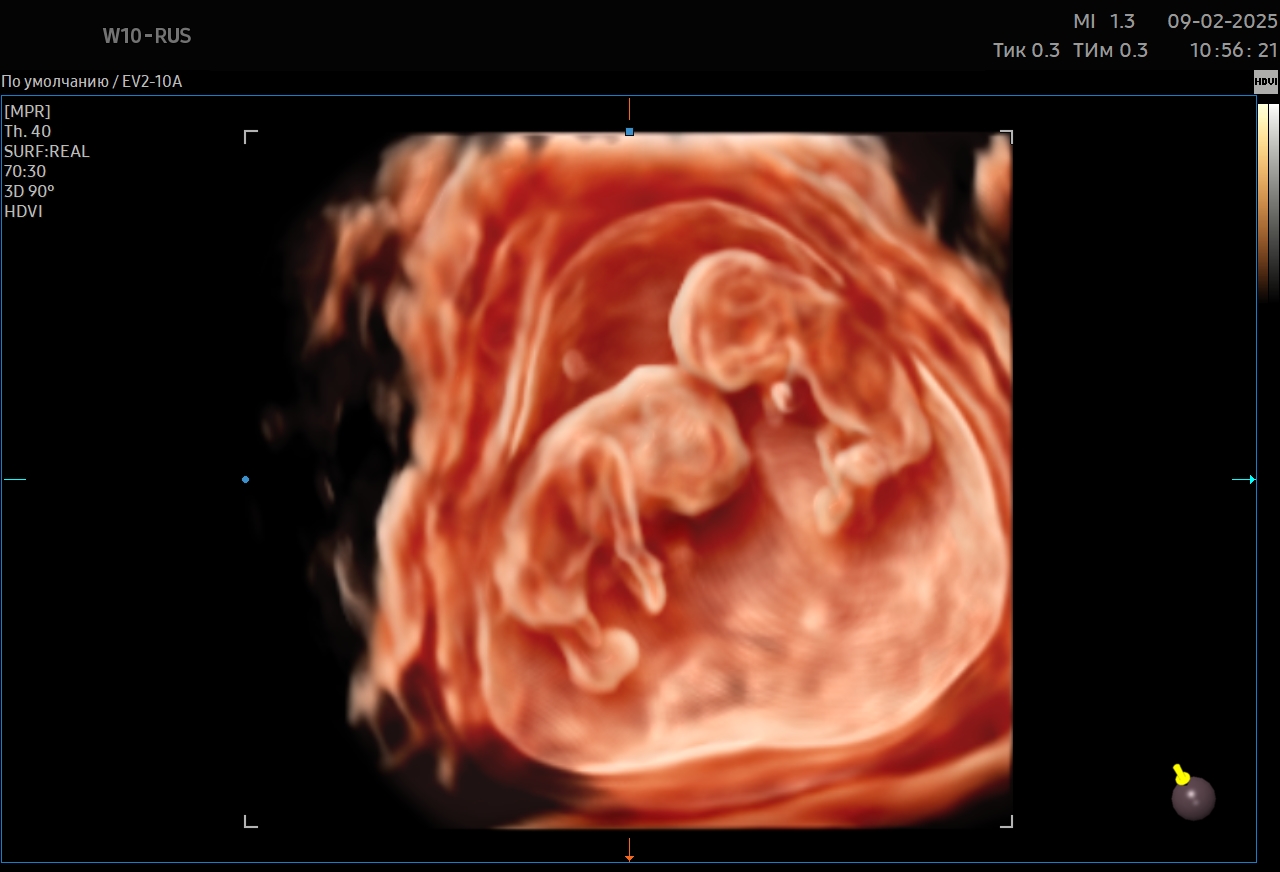

Ультразвуковое исследование – это наиболее информативный метод диагностики состояния плода и беременной женщины. В «Мать и дитя» оно проводится с помощью современного ультразвукового оборудования, которое формирует максимально детализированное изображение. УЗИ дает возможность обнаружить особенности развития малыша на самой ранней стадии. Метод абсолютно безопасен и может выполняться любое количество раз.

При необходимости врач назначает дополнительные измерения, оценивает кровоток (допплерометрия) или проводит экспертное исследование, чтобы уточнить состояние плода и выбрать оптимальную тактику наблюдения.